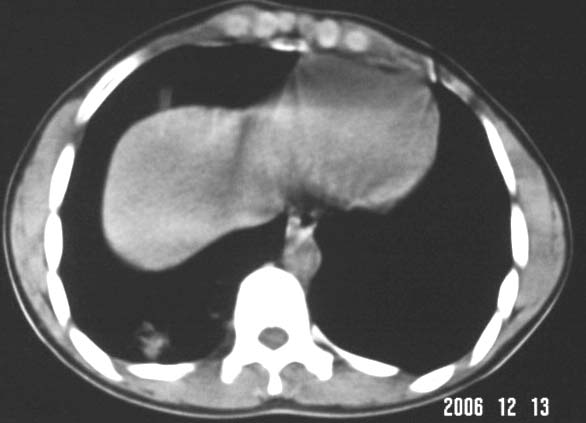

标题: CT5614:外伤病人男,20岁,右上腹痛.余肺野(-) [打印本页]

标题: CT5614:外伤病人男,20岁,右上腹痛.余肺野(-)

其次,病灶较多并散布在右下肺底,纵肺比例明显小于50%,与膈肌以及后壁胸膜有轻度粘连。且其内密度不均匀,最大的那个结节影里面有较致密密度,胸椎旁似乎还有液平面。也就是说右下肺炎性改变可以肯定。

外伤病人男,20岁,右上腹痛,ct显示:右肺下叶后基地段见斑片状高密度影,密度不均,边界清,考虑1,右肺下叶肺挫伤;2,炎症。